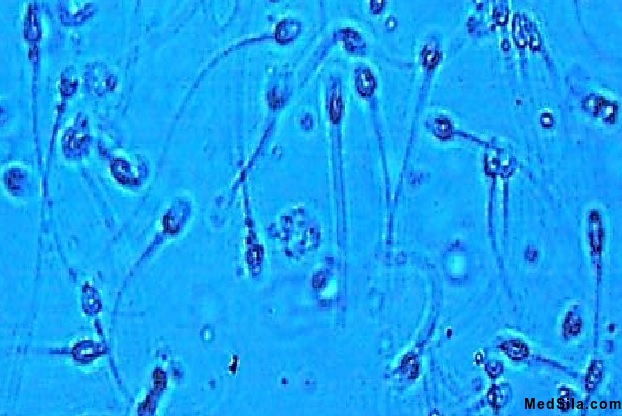

Спермограмма – анализ по исследованию спермы (семенной жидкости) под микроскопом. Данный анализ назначает врач – андролог или врач – уролог для уточнения причины мужского бесплодия, профилактики и лечения мужской дисфункции. Для исследования семенной жидкости необходима тщательная подготовка, о которой накануне сообщает лечащий врач.

- Общее количество сперматозоидов в эякуляте (сперме) не менее 40 млн. Количество сперматозоидов в 1 мл. – до 20 млн/мл. После оценки общих параметров врач лабораторной диагностики проводит микроскопическое исследование (под микроскопом). Под объективом микроскопа врач – лаборант оценивает подвижность сперматозоидов (оценивается быстрота поступательных движений), форму сперматозоидов (наличие всех частей у активного сперматозоида - головки, шейки (средняя часть), хвоста), жизнеспособность (наличие незначительного количества мертвых сперматозоидов может носить временных характер, например, при тяжелых отравлениях), наличие склеенных (агглютинированных) сперматозоидов (в норме их быть не должно, иногда встречается при иммунной патологии).